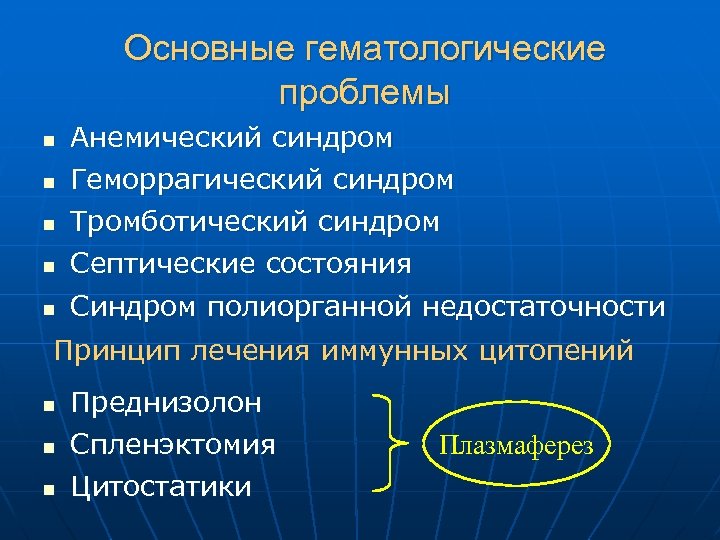

Основные гематологические проблемы n Анемический синдром Геморрагический синдром Тромботический синдром n Септические состояния n Синдром полиорганной недостаточности n n Принцип лечения иммунных цитопений n n n Преднизолон Спленэктомия Цитостатики Плазмаферез